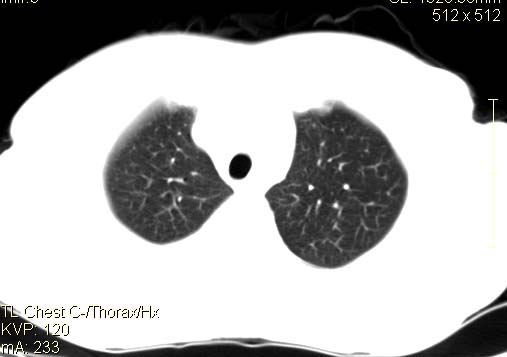

以下是引用qingyuan在2007-4-17 14:19:00的发言:[br]右肺下叶外侧后段胸膜下区节结样病变、分叶、内可见空洞,壁厚薄不均,胸膜凹陷、肺门周围区纹理增粗、僵硬、并近似小结节样改变,肺门区软组织节结、纵膈淋巴结肿大,患者病史长、抗炎治疗无好转炎性改变基本排除,考虑:右肺下叶周围型肺癌伴纵膈及右肺门区淋巴结转移、肺内淋巴管受侵。